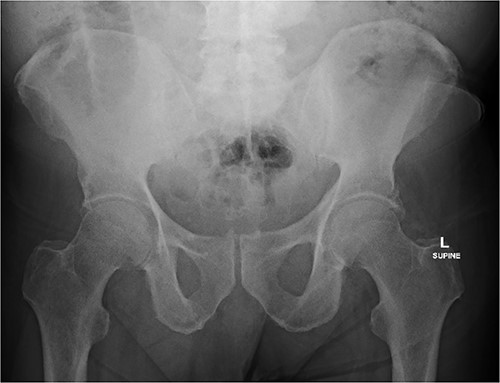

An 80 year old male presented to the emergency department after accidentally swallowing his hearing aids. On presentation he was pain free, hemodynamically stable, and had a soft abdomen. He had a background of type-2 diabetes, rheumatoid arthritis and diverticulitis. The hearing aids were powered by lithium battery. X-ray found two foreign bodies in the left upper abdomen (Fig. 1). After assessment in the emergency department, he returned home to await their natural passage. One hearing aid was found in his stools the following day, but he represented three weeks later as the second hearing aid remained unaccounted for. He underwent repeat abdominal x-ray and CT, which found the hearing aid retained within a presumed distal duodenal diverticulum (Figs 2 and 3). He was booked a push enteroscopy the following day.

Abdominal CT identifying one hearing aid in a jejunal diverticulum 3 weeks after initial presentation – axial view.